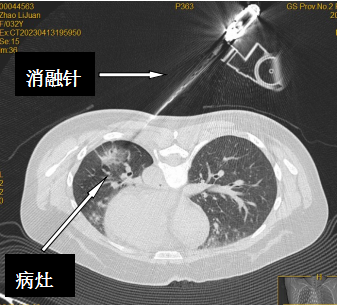

术前团队详细向赵女士讲解了手术过程,消除了她紧张的情绪,手术中采取了局部麻醉,进一步保证了手术的安全和疗效。治疗过程中通过CT引导下精准定位,引导冷冻消融针进入肿瘤内,利用氩气在1分30秒内使消融针温度达到-196℃,持续10分钟后,使用氦气复温至消融针温度80℃,持续治疗5分钟,反复调整消融针位置进行3次治疗后复查胸部CT,冷冻治疗后病灶超过原来病灶1cm以上,无气胸及出血等并发症,手术顺利结束。